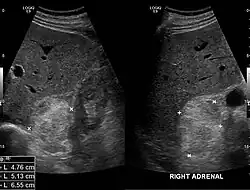

Pathologie

Myelolipome sind gelbe bis bräunliche, wenige Millimeter bis 30 cm große, umschriebene, jedoch nicht gekapselte Tumoren. Sie treten üblicherweise solitär und einseitig im Bereich einer Nebenniere auf, werden selten jedoch auch bilateral und/oder außerhalb der Nebenniere (z. B. im Retroperitoneum, Mediastinum, der Leber, in Muskelfaszien) gefunden. Mikroskopisch setzt sich der Tumor aus reifem Fettgewebe und myeloiden Zellen zusammen. Gelegentlich werden Infarktareale, Einblutungen oder knöcherne Metaplasien beobachtet.[1][2]

Die Mehrzahl der Myelolipome sind asymptomatisch und werden zufällig, etwa im Rahmen radiologischer Untersuchungen oder einer Obduktion gefunden. Nur gelegentlich, insbesondere bei größeren Tumoren, berichten betroffene Patienten von Bauch- oder Flankenschmerz. Selten bestehen endokrine Störungen wie das Cushing-, Conn-Syndrom oder eine angeborene Nebennierenhyperplasie.[1]